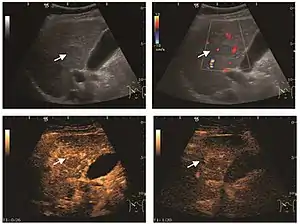

HCC appearance on 2D ultrasound is that of a solid tumor, with imprecise delineation, with heterogeneous structure, uni- or multilocular (encephaloid form). An "infiltrative" type is also described which is difficult to discriminate from liver nodular reconstruction in cirrhosis. Typically HCC invades liver vessels, primarily the portal veins but also the hepatic veins . Doppler examination detects a high speed arterial flow and low impedance index (correlated with described changes in tumor angiogenesis). The spatial distribution of the vessels is irregular, disordered. CEUS examination shows hyperenhancement of the lesion during the arterial phase. During the portal venous phase there is a specific "wash out" of ultrasound contrast agent (UCA) and the tumor appears hypoechoic during the late phase. Poorly differentiated tumors may have a stronger wash out leading to an isoechoic appearance to the liver parenchyma during portal venous phase. This appearance was found in approx. 30% of cases. The described changes have diagnostic value in liver nodules larger than 2 cm.

On CEUS examination, early HCC has an iso- or hypervascular appearance during the arterial phase followed by wash out during portal venous and late phase. There are studies showing that the wash out process is directly correlated with the size and features of neoplastic circulatory bed. Thus, highly differentiated HCC illustrates the phenomenon of late or even very late "wash out" while poorly differentiated HCC has an accelerated wash out at the end of arterial phase. It is therefore mandatory to analyze all these three phases of CEUS examination for a proper characterization of liver nodules. Tumor wash out at the end of the arterial phase allows the HCC diagnosis with a predictability of 89.5%. Some authors consider that early pronounced contrast enhancement of a nodule within 1–2 cm developed on a cirrhotic liver is sufficient for HCC diagnosis. These results prove that for a correct characterization of the lesions it is necessary to extend the examination time to 5 minutes or even longer.